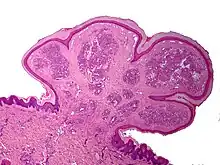

One study has suggested a correlation between pyogenic granulomas and Bartonella seropositivity.[8] However, this association has been questioned by others.[9] The microscopic appearance of a pyogenic granuloma consists of highly vascular granulation tissue. Inflammation is present. The lesion may have a fibrous character if it is older, and the surface may have ulcerations. Pyogenic granulomas rarely occur in the conjunctiva, cornea, or connective tissue of the eye following minor local trauma. Grossly, these mass lesions resemble those occurring at more common sites. The relationship of these lesions to lobular capillary hemangiomas of skin and oropharyngeal mucosa commonly referred to as pyogenic granuloma is uncertain.

Histopathological examination shows multiple capillaries (due to the vascular nature of the tumor), neutrophils (pyogenic), and necrotic tissue.